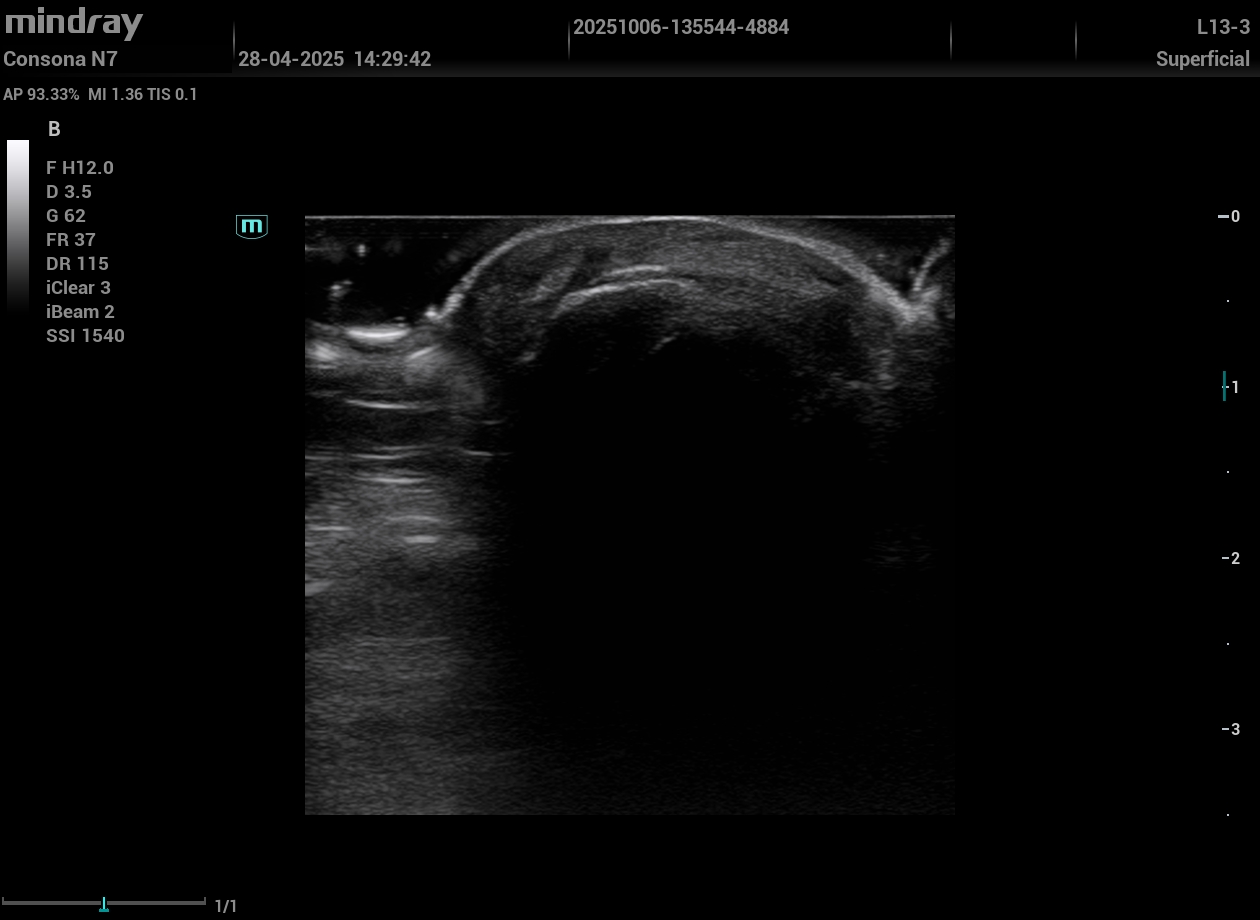

Paciente con dislipemia: no podíamos calcular su riesgo cardiovascular, hicimos una ecografía de carótidas y femorales donde se visualizaron placas de ateroma subclínicas. Con esa imagen, iniciamos tratamiento hipolipemiante con confianza y sin demoras.